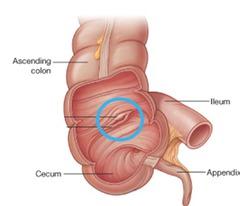

Ascending/transverse/descending/sigmoid colon

Cecum

Ileocecal valve

Ileum

Vermiform appendix